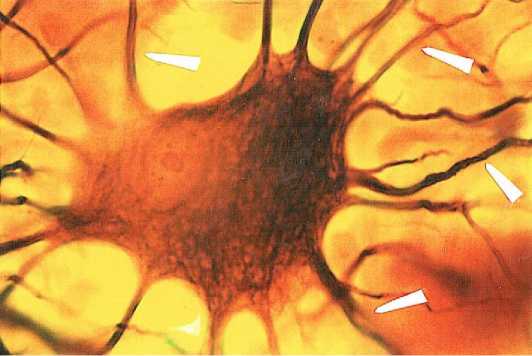

Процесс формирования истинной нейрофиб-риллярной сети происходит на всех стадиях дифференцировки нейробластов, и у новорожденных, и у людей I зрелого возраста. На препаратах, им-прегнированных универсальным методом, это проявляется образованием в нейроплазме аргирофильной зернистости, затем более интенсивной, но не гомогенной импрегнацией всей нейроплазмы, и завершается идентификацией в ней нейрофибриллярной сети, продолжающейся во все отростки дефинитивных нейроцитов (рис. 4).

Рисунок 4. Нейрофибриллярная сеть в нейроплазме нейро-цита подслизистого сплетения тонкой кишки женщины I зрелого возраста. ↑) нейрофибриллы в отростках. Универсальный метод импрегнации. Ув. 900

Figure 4. Neurofibrillary network in the neuroplasm of a neurocyte of the submucosal plexus of the small intestine of a mature woman. ↑) neurofibrils in processes. Universal impregnation method. Mag. 900